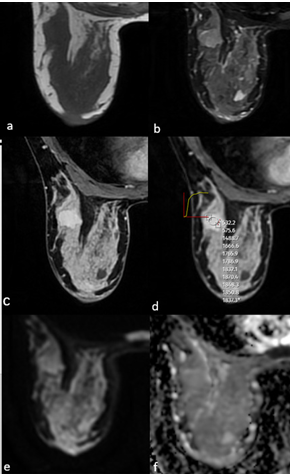

18 (72%) CFAs and 19 (76%) PTs showed heterogeneous enhancement in early sequences after contrast administration. However, on delayed phase T1WI, 10 (40%) of the CFAs and 18 (72%) of the PTs sustained heterogeneous enhancement characteristics. This finding was noted as statistically significant (p=0.023). Signal intensity / time curve demonstrated type one pattern in majority of the cases, 18 (72%) of the CFAs and 17 (68%) of the PTs. seven (28%) CFAs and seven (28%) PTs had type 2, one (4%) PT had type 3 pattern. Among CFAs, one (4%) had enhancing and 18 (72%) had non-enhancing internal septations, whereas among PTs, four (16%) of them were enhancing and 16 (64%) were non-enhancing. Pseudocapsulation was seen in 12 (48%) of the CFAs and seven (28%) of the PTs. Two(8%) CFAs and nine (36%) PTs had cystic components and this result was also statistically significant (p=0.017, Table 2). MRI examples of CFA and PT are shown in Figures 1 and 2.

Figure 2. MRI of a 43-year-old female patient showed a well-circumscribed solid mass with microlobulated contour, isointense on T1WI (a), heterogeneous hyperintense on T2A (b), homogeneous contrast enhancement on postcontrast T1WI (c), type 2 signal intensity/time curve (d), and no significant diffusion restriction on DWI (e,f). After excision, the pathological diagnosis was borderline phyllodes tumour